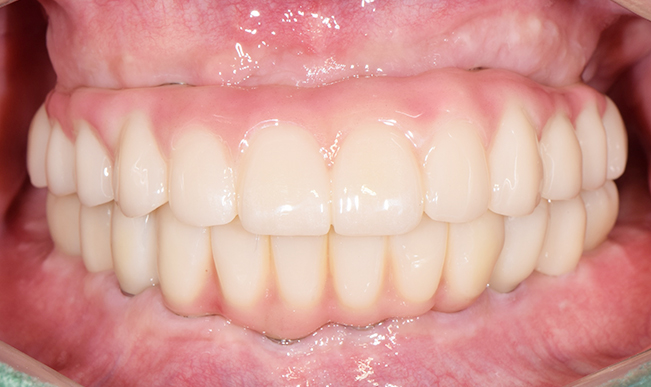

본 사진은 환자분의 동의하에 게재하였습니다.